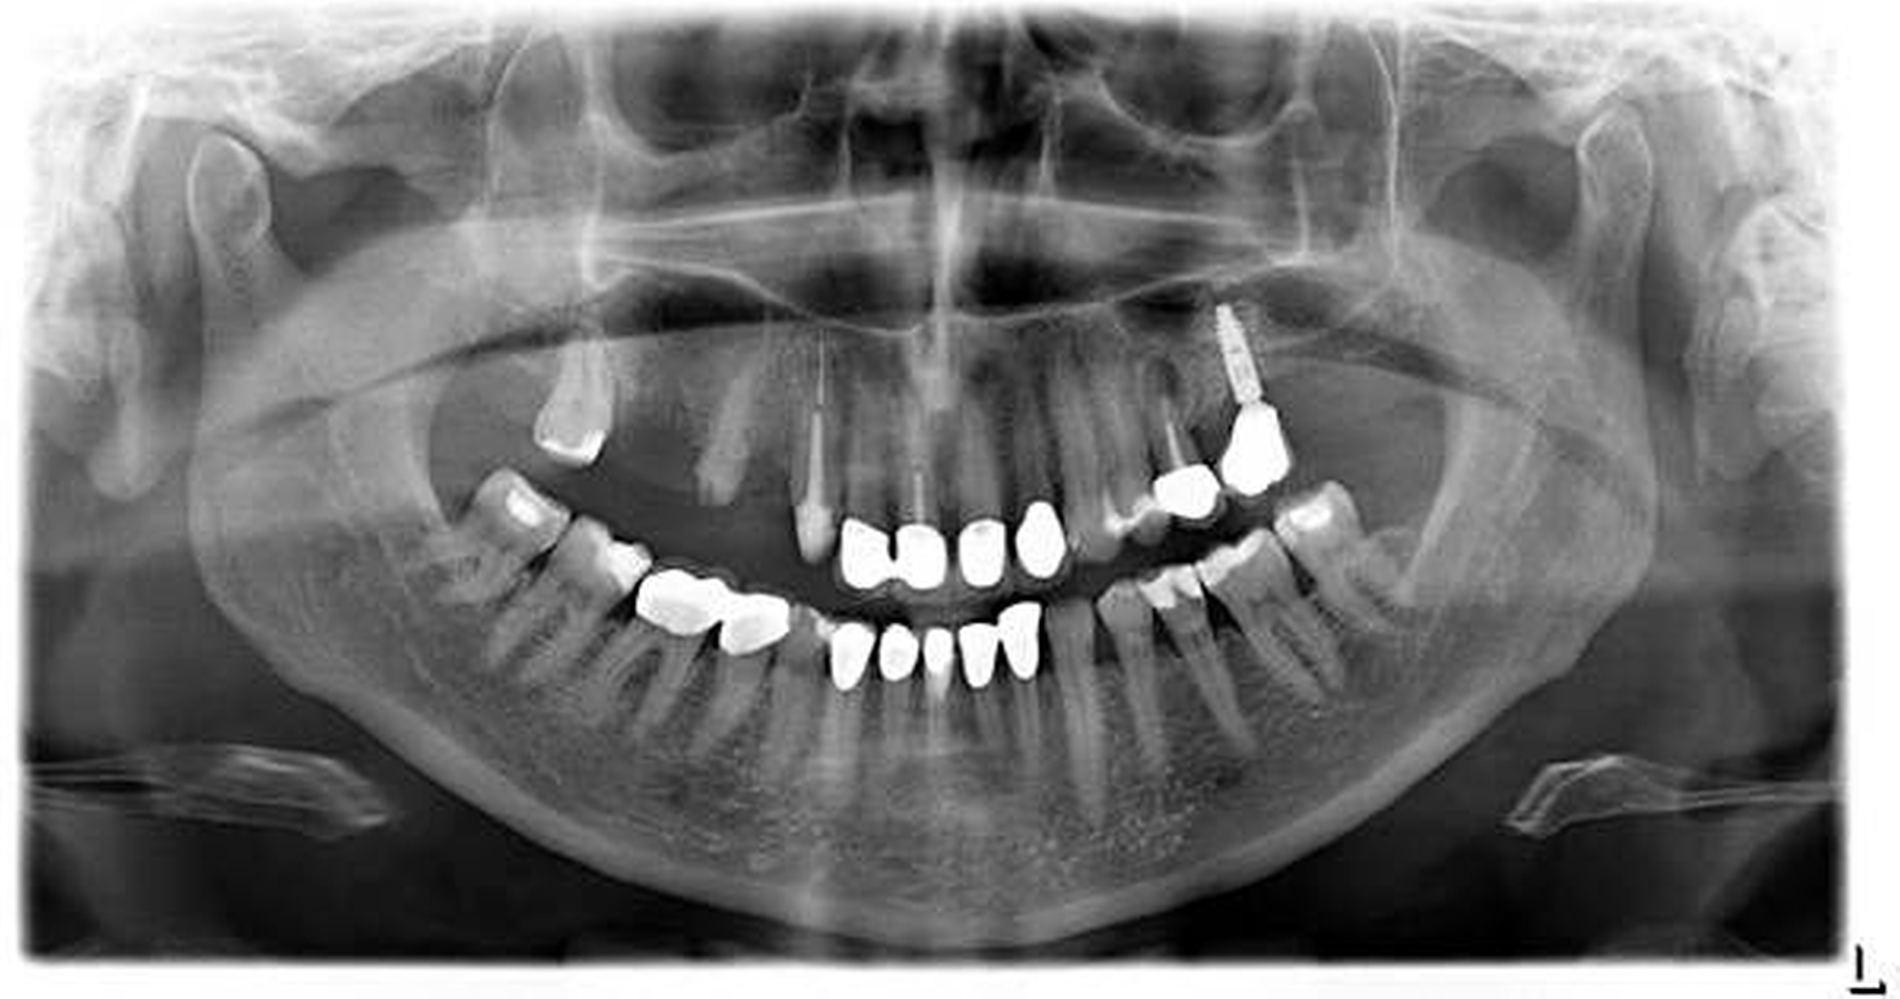

Erneut vorstellig bei ihrem behandelnden Zahnarzt habe die Patientin um die Anfertigung eines Röntgenbildes gebeten, was nach ihren Angaben allerdings abgelehnt worden sei. Nach Überweisung zu einem niedergelassenen MKG-Chirurgen fertigte dieser ein Orthopantomogramm (Abbildung 1) an, auf dem eine deutliche Verschattung im Bereich der rechtsseitigen Kieferhöhle festgestellt wurde, woraufhin er sie zur Weiterbehandlung an das Universitätsklinikum Regensburg überwies.

Bereits am ersten postoperativen Tag wurde erneut ein Orthopantomogramm (Abbildung 5) zur Kontrolle angefertigt. Die Wundheilung zeigte sich stadiengerecht, die Kieferhöhlentamponade konnte am fünften postoperativen Tag entfernt werden. Die histopathologische Untersuchung der Kieferhöhlenbioptate ergab das Vorliegen einer stärkergradig chronischen, sowie mäßiggradigen floriden Entzündung der Schleimhaut des Sinus maxillaris rechts.